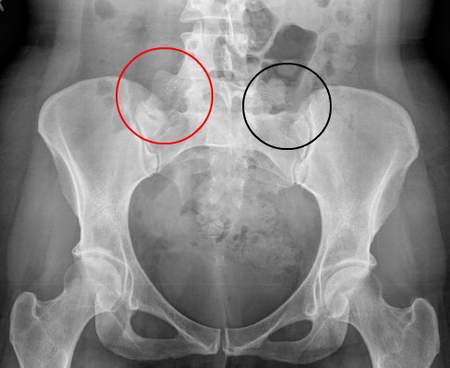

Bạn bác sĩ cũng có thể yêu cầu chụp X-quang để xác nhận. Chụp MRI có thể được sử dụng nếu bác sĩ nghi ngờ bạn bị viêm cột sống dính khớp.